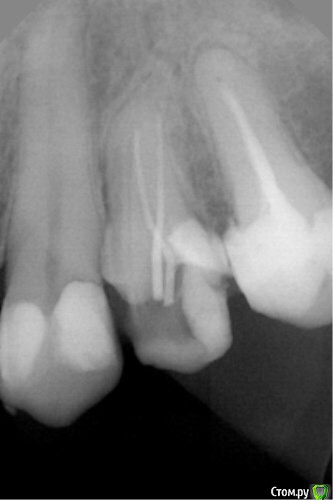

dr.Dre Опубликовано 13 апреля, 2016 Поделиться Опубликовано 13 апреля, 2016 Добрый день коллеги,24 зуб что скажете по снимку есть 3 канал?Два канала кальцинированы ввожу 10 к файл ничего,20 цепляет? Ссылка на комментарий